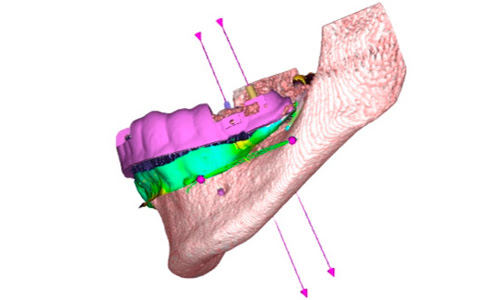

Bone Grafting

Through this course, dentists can learn scientific and surgical techniques to perform advanced bone grafting procedures. The course is expanded through a series of lectures, workshops, and collaborative instruction. Dentists will receive training on diagnosing and planning for bone grafting procedures as well. Advanced imaging techniques are also provided to dentists attending the course. The primary objective is to provide dentists with the expertise to perform comprehensive bone grafting treatments.